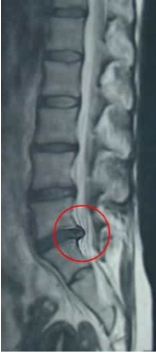

Un’ernia o protrusione del disco ha luogo con più frequenza nella parte bassa o lombare della schiena. È una delle cause più comuni di dolore lombare. Il dolore sciatico, la lombosciatica o lombosciatalgia sono spesso dovute alla compressione della radice nervosa esercitata da un’ernia discale lombare. La diagnosi differenziale che si deve scartare, poiché provoca una sintomatologia simile, è quella di Sindrome delle faccette articolari lombari .

La tecnica chirurgica più utilizzata nelle ernie o protrusioni lombari è la discectomia via semi-emi-laminectomia. I risultati nel nostro centro sono eccellenti per la maggior parte, con un numero di complicazioni minimo.

Esempio